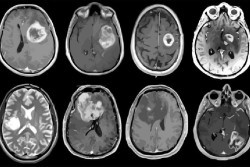

Descubierto nuevo objetivo de inmunoterapia para tumores cerebrales malignos

Los científicos aseguran haber descubierto un nuevo objetivo potencial para la inmunoterapia de los tumores cerebrales malignos, que hasta ahora se han resistido a la inmunoterapia, el innovador tratamiento del cáncer basado en el aprovechamiento del sistema inmunológico del cuerpo. El descubrimiento, publicado en la revista `CELL`, de momento no tiene implicaciones inmediatas para el tratamiento de los pacientes, advierten los investigadores.